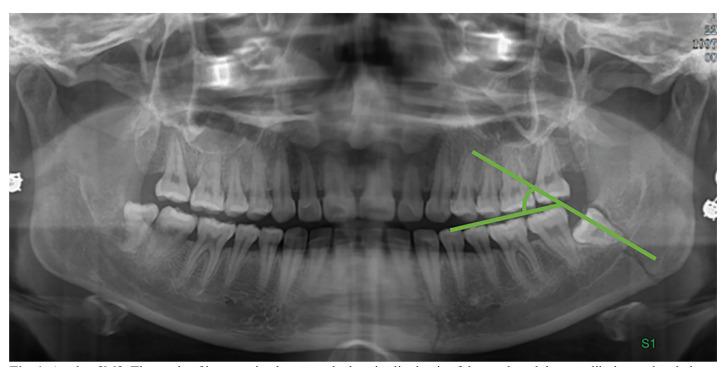

Assess the correlation between the position of the third molar (M3) and fractures of the mandibular angle and condyle using panoramic radiographs to offer valuable data references for oral clinical research.

A retrospective cross-sectional study was undertaken, involving the collection of 409 cases of mandibular fracture in the Yanbian University Hospital. The case records and panoramic radiographs of mandibular angle fracture (78 cases) and condylar fracture (106 cases) were evaluated.

In the comparative analysis between the mandibular angle fracture group and the condylar fracture group, statistical significance was observed in the variables of M3 existence (P = 0.002), eruption of M3 from the alveolar cavity (P = 0.003), P&G position classification (P = 0.001), deep impactions (Classes IC, IIC, IIIB, and IIIC) (P < 0.001), and the presence of impacted M3 in both groups (P < 0.001).Regarding M3 roots, the mandibular angle fracture group exhibited the highest prevalence of multiple roots at 75.4%, surpassing the 64.6% observed in the condylar fracture group. The prevalence of proximal angles in the mandibular angle group and the condyle group was the highest, accounting for 64.6% and 61.5%, respectively. The percentage of M3 in the two groups was 80% and 43.1%, respectively, with a significant difference (P < 0.001).

Impacted mandibular third molars (M3) elevate the risk of mandibular angle fractures, while their absence or normal eruption reduces this risk and protects against condylar process fractures. The fracture risk is influenced by the M3's position: P&G Class II and Class B impactions, where M3s emerge partially from the alveolar bone, are significantly associated with mandibular angle fractures. In contrast, the absence of M3 or its placement in P&G Class I and Class A positions tends to correlate with a higher incidence of condylar process fractures.